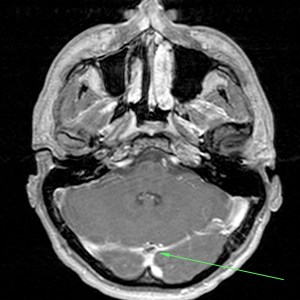

Se procede a la intervención de la paciente con realización de Arteriografía.